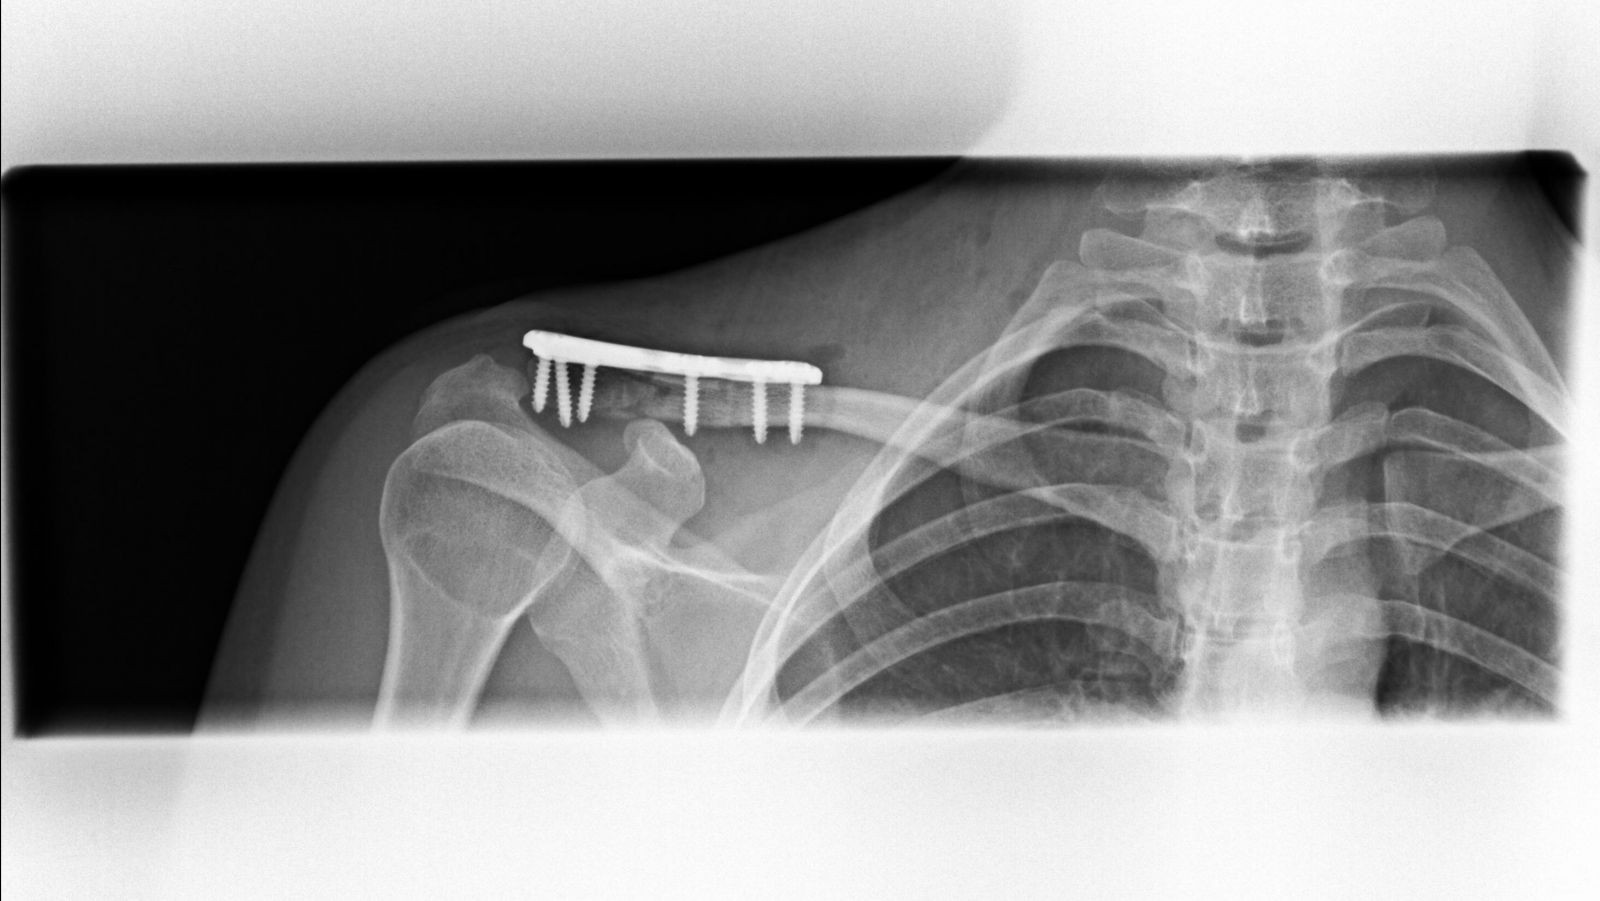

Μετεγχειρητικά, οστεοσύνθεση κατάγματος και αποκατάσταση κορακοκλειδικών συνδέσμων